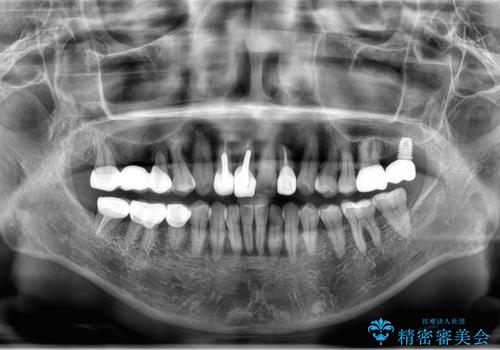

- 前歯のかぶせ物のやりかえと、全体的な治療をご希望して来院。

左上は他院でインプラントを入れたが、クラウンの脱離を繰り返して、仮歯に戻したあともうそれでいいと言われたとのことでした。

仮歯はすっかり劣化、変質しており、上記の写真のように隣の歯が虫歯になっている状態でした。

インプラントの製造会社は当院で使っているものと異なったため、ドライバー等購入し対応しました。

全体的にプラスチックで治療してあり、劣化していたのと、また、右上6番は根の治療がされていましたがプラスチックで埋めてあるだけで中を見たところ残念ながら割れていました。その歯は抜歯し⑤6⑦ブリッジにしています。

全体的にしっかり治療を行い、メンテナンスにはいることができました。